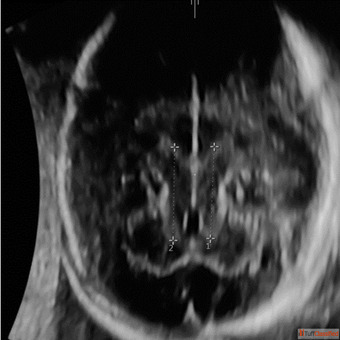

Welcome to Fetal India! Our Fetal Neurosonography service is designed to provide you with a clear and detailed image of your baby's brain development. With state-of-the-art technology and experienced technicians, we ensure that you receive accurate and reliable information about your little one's health. Trust Fetal India for a comprehensive and caring experience.

Click here- https://www.fetalindia.com/dedicated-scan-for-fetal-neurosonography